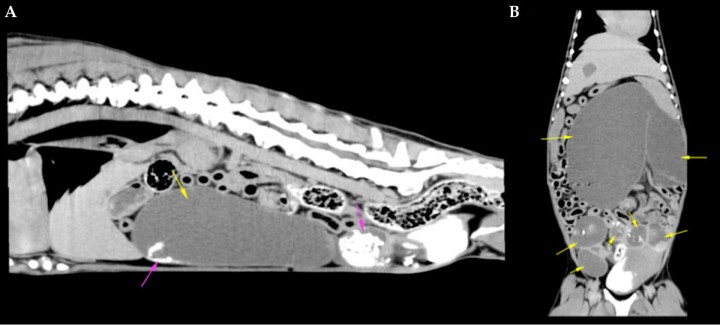

Para una valoración completa del abdomen y descartar posibles complicaciones no visibles en la ecografía, se recomendó la realización de una tomografía computerizada (TC) abdominal prequirúrgica en la que se observó el útero muy distendido con contenido líquido y estructuras hiperatenuantes mineralizadas, apreciándose el mismo patrón en espiral o signo de remolino característico de torsión visto en ecografía, que afectaba al cuerno uterino izquierdo (Fig. 5) (Vídeo 2), sin otros hallazgos significativos.

<p>Tomografías computerizadas prequirúrgicas del abdomen. (<strong>A</strong>) Corte sagital. (<strong>B</strong>) Corte dorsal. Se observa una gran distensión uterina con contenido líquido (flechas amarillas) y estructuras hiperatenuantes mineralizadas en su interior (flechas rosas).</p>

Tomografías computerizadas prequirúrgicas del abdomen. (A) Corte sagital. (B) Corte dorsal. Se observa una gran distensión uterina con contenido líquido (flechas amarillas) y estructuras hiperatenuantes mineralizadas en su interior (flechas rosas).